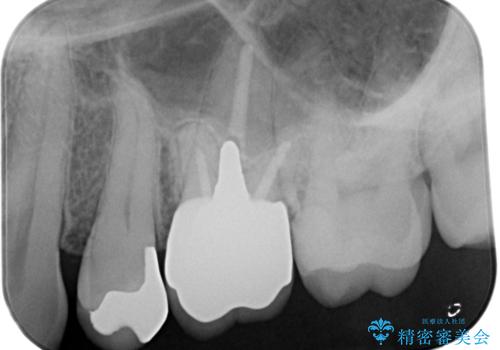

- 銀歯を白くしたいとの事で来院。まずは気になるところから治療していくという事になりました。

銀の被せ物を外し虫歯がないのを確認して、形を整えて白い被せ物の治療を行いました。

(再根管治療の提案をしたがご希望されませんでした。)